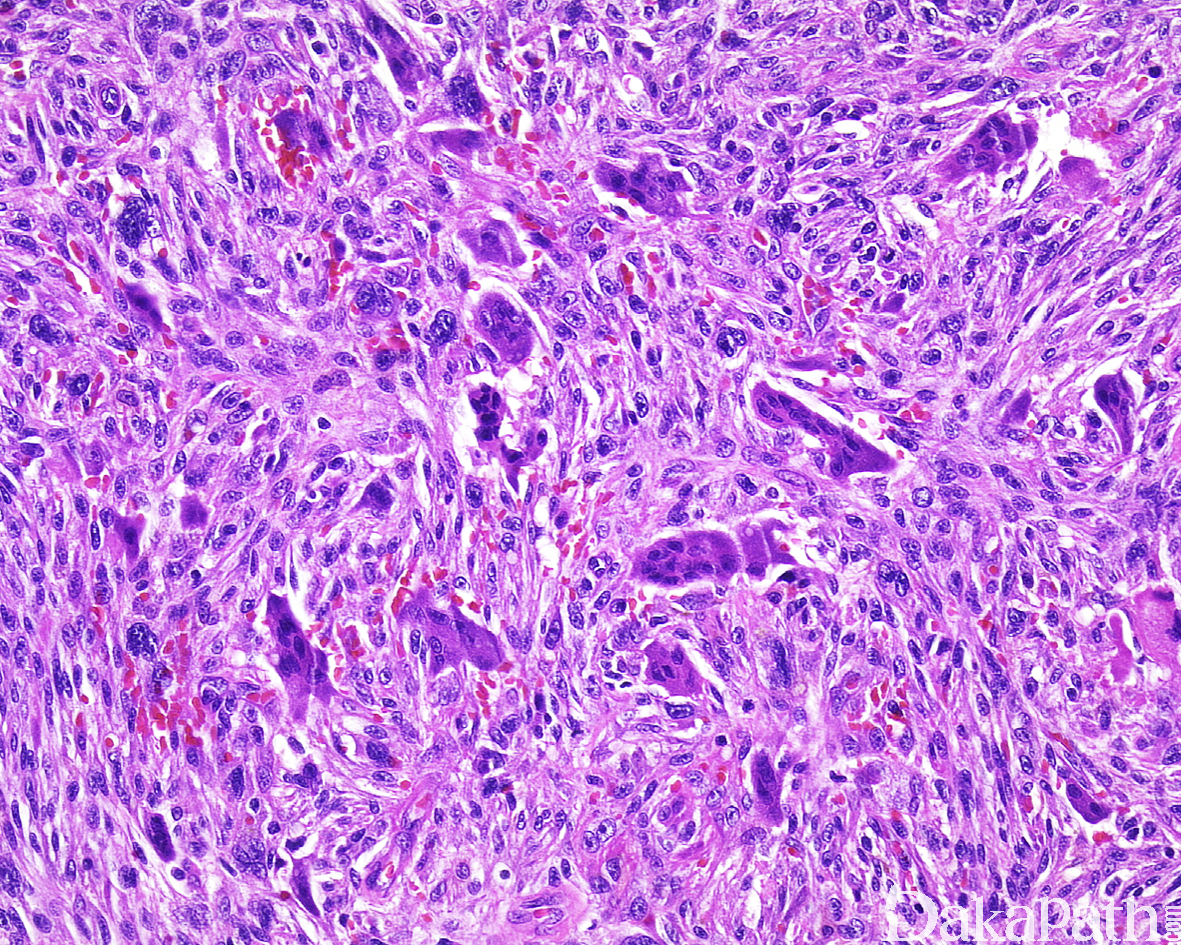

镜下肿瘤无包膜,通常边界清楚,梭形细胞多杂乱排列,有时可呈束状排列;

散在明显异型及多形性细胞,畸形细胞以及单核或多核瘤巨细胞,胞浆嗜酸、淡染、透明、颗粒均可见;

核分裂像易见,可见病理性核分裂像;

部分病例可完全由条束状排列的梭形细胞组成,瘤细胞并无明显的多形性,也可以上皮样细胞为主;

有些病例可含有破骨样多核巨细胞,也有病例可见胞质透亮或颗粒样瘤细胞;

多少不等的炎细胞浸润背景,可伴明显的胶原化或硬化。